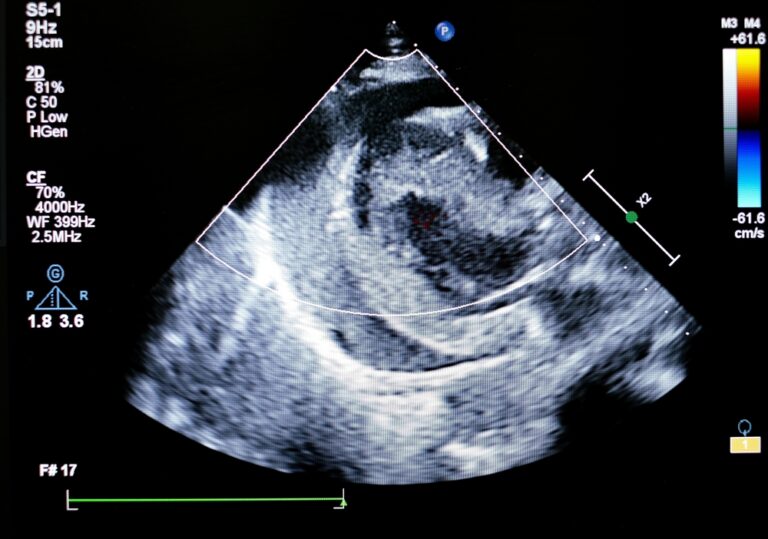

How an Echocardiogram Helps Detect Heart Problems

An echocardiogram is one of the most widely used tools in cardiology and for good reason. It offers a safe, noninvasive way to evaluate the